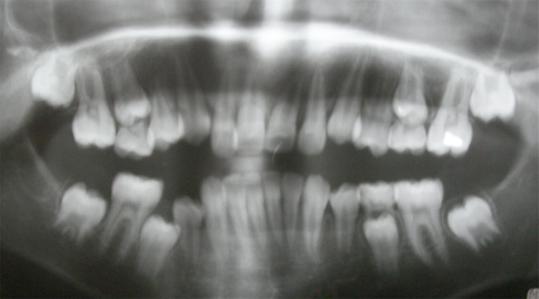

Space regaining: To regain space that had been lost to mesial drifting or inclination of posterior teeth. As permanent molars drift or incline in to the space after early extraction of milk tooth. This blocks the proper eruption of premolar.

- Normal eruption of impacted tooth.